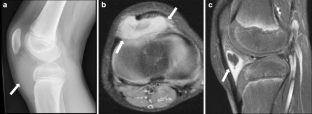

Synovium is the thin membranous lining of a joint. It produces synovial fluid, which lubricates and nourishes the cartilage and bone in the joint capsule. Synovial diseases in children can be classified as normal structures as potential sources of pathology (synovial folds: plicae, infrapatellar fat pad clefts), noninfectious synovial proliferation (juvenile idiopathic arthritis, hemophilic arthropathy, lipoma arborescens, synovial osteochondromatosis, pigmented villonodular synovitis, reactive synovitis), infectious synovial proliferation (pyogenic arthritis, tuberculous arthritis), deposition disease (gouty arthropathy), vascular malformation, malignancy (metastasis) and intra-/periarticular cysts and cyst-like structures. Other intra-articular neoplasms, such as intra-articular synovial sarcoma, can mimic synovial disease in children.